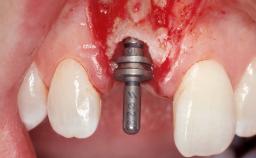

A 29-year-old female patient presented for treatment to replace the upper left central incisor tooth with an implant- supported restoration. The tooth had been intermittently symptomatic for the previous 12 months. The tooth had originally suffered trauma about 15 years previously. Several endodontic treatments had been performed, including an apicectomy procedure to retain the tooth. The patient was healthy and a non-smoker. She had reasonable expectations in regard to esthetic outcomes and the risk of marginal tissue recession following treatment. At medium smile, the gingival margins of the upper teeth were visible, with a display of 3 to 4 mm of the gingival margins. Gingival recession of tooth 21 and a discrepancy in the gingival levels between teeth 11 and 21 was observable during normal speech and smile.

| Placement Protocol | Immediate implant placement |

| Tooth Site | Maxillary incisor or canine |

| Retention | Screw-retained Screw-retained |